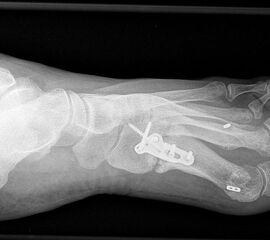

Die dorsoplantaren Röntgenaufnahmen zeigen eine Open-wedge Technik mit der normalerweise ein erhöhter intermetatarsaler Winkel gut zu korrigieren ist (Abbildung 3). Die Wirksamkeit einer Basisosteotomie ist umso größer, je proximaler diese durchgeführt wird. Je weiter distal die Osteotomie, umso geringer die Korrektur. Auf den postoperativen Bildern ist der distal unverändert große Abstand zwischen Metatarsale I und Metatarsale II erkennbar, bei gleichzeitiger Subluxation des Großzehengrundgelenks und dezentrierten Sesambeinen. Darüber hinaus finden sich initiale degenerative Veränderungen im Großzehengrundgelenk. Klinisch bestand eine hohe Weichteilspannung, bei verkürzter Extensor- und Flexor hallucis longus Sehne.  Daher wurde ein verkürzendes Verfahren zur Revision gewählt (Abbildung 4). Die Lapidusarthrodese stellt ein sehr zuverlässiges Verfahren zur Behandlung von Hallux valgus Rezidiven dar 9. Die Fusion des Tarsometatarsale-I-Gelenks kombiniert Stabilität mit einem hohen Korrekturpotenzial. Aufgrund der verfahrensimmanenten Verkürzung des ersten Strahls und der in diesem Fall bereits präoperativ vorhandenen Transfermetatarsalgie wurde die Entscheidung für eine verkürzte Weil-Osteotomie am zweiten bis fünften Strahl gefällt. Die Kombination beider Verfahren führte zu einem homogenen Metatarsale-Index und zu einer gleichmäßigen plantaren Druckverteilung 10. Die Hallux valgus interphalangeus Fehlstellung wurde mit einer Akin-Osteotomie korrigiert.